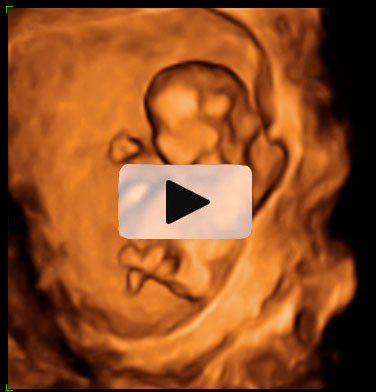

Ecografía Embarazo 2D y 3D Semana 12 - ANOMALÍAS CROMOSÓMICAS